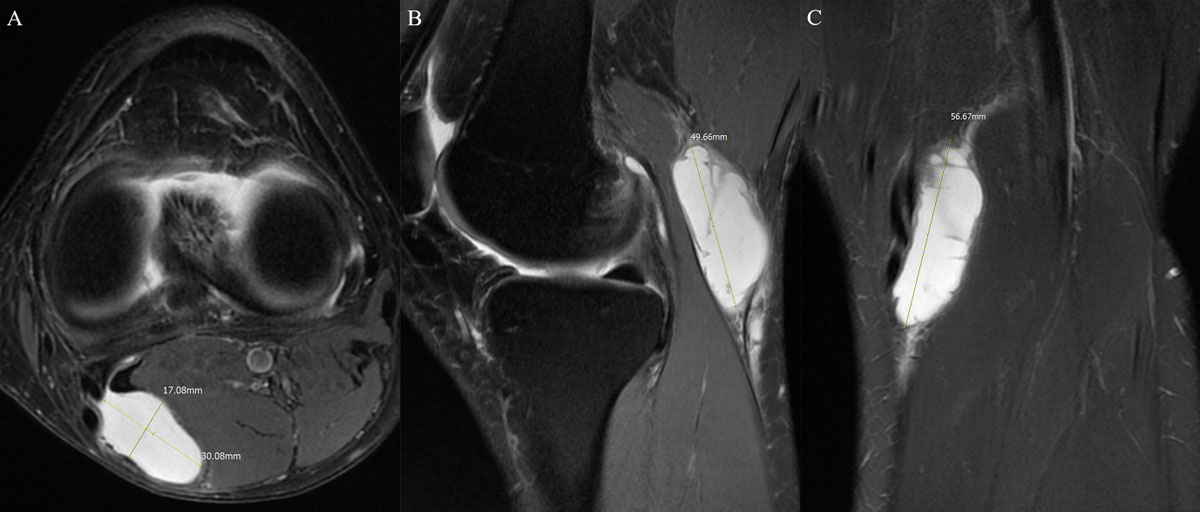

Ressonância magnética

A ressonância magnética é especialmente importante quando se deseja estudar a articulação como um todo, identificando menisco, cartilagem, artrose, derrame articular, sinovite e outras alterações associadas. Na prática, ela ajuda a explicar por que o cisto apareceu.

Ultrassonografia e ressonância magnética são os exames mais usados. A ressonância ajuda ainda a investigar artrose, menisco e outras alterações do joelho.